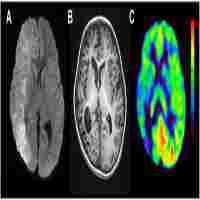

| Abstract | Focal cortical dysplasia (FCD) is a major cause of intractable epilepsy in children however the mechanisms underlying the pathogenesis of FCD and FCD induced epilepsy remain unclear. Increasing evidence suggests that the large-pore ion channels, pannexin 1 (Panx1) and 2 (Panx2), are involved in epilepsy and brain development. In this study, we investigated the expression of Panx1 and Panx2 in surgical samples from patients with FCD type Ia (FCDIa), type IIa (FCDIIa), and type IIb (FCDIIb) and in age-matched autopsy control samples. We found Panx1 mRNA and protein levels were both increased in all these FCD samples. Immunohistochemical analyses revealed that Panx1 was mainly distributed in microcolumn neurons, dysmorphic neurons (DNs), balloon cells (BCs) and reactive astrocytes. Double-labeled staining showed that the Panx1-positive neurons were mostly glutamatergic DNs and occasionally GABAergic normal-appearing neurons. Importantly, the protein levels of Panx1 positively correlated with the frequency of seizures. Intriguingly, the Panx2 mRNA and protein levels were only upregulated in FCDIIb lesions and characteristically expressed on SOX2-positive multipotential BCs. Immunofluorescent experiments identified that Panx2-positive BCs mainly expressed the neuronal differentiation transcription factor MASH1 but not the immature glial marker vimentin. Taken together, our results established a potential role of the specific expression and cellular distribution patterns of Panx1 and Panx2 in FCD-associated epileptogenesis and pathogenesis. |